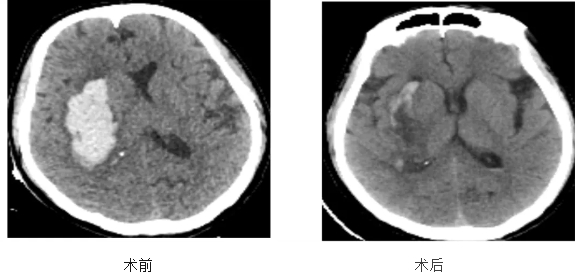

8月19日上午,在患者李奶奶手术结束不久,52岁的王先生(化姓)因在工作中突发意识不清伴左侧肢体不能活动,被家属紧急送往省第三人民医院阳逻院区神经外科重症监护室。急诊头颅CT显示右侧基底节出血。神经外科主治医师尧小龙接诊患者,对患者的病情及检查结果进行了详细分析,判断患者目前出血量符合手术指征。

为及时挽救患者生命,神经外科团队迅速召开线上会议,制定了严密的手术方案。考虑患者实际情况及病情发展,与家属充分沟通后,神外团队于术前应用3D血肿重建“模拟手术”,争取以最小的创伤最大程度清除脑内血肿。术中在神经内镜下行基底节区血肿清除术,过程顺利。

术后第一天患者意识清楚。复查头颅CT可见右侧基底节区脑内血肿已完全清除,脑组织及脑室受压解除,中线结构居中,颅骨缺损直径约1cm。经过两周的专业治疗,患者于9月2日顺利康复出院。